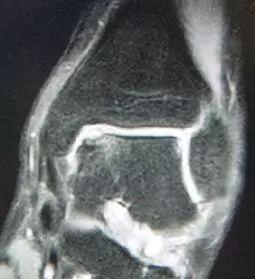

踝关节“反复扭伤”是踝关节不稳的一种表现,也是一种疾病,必须得到重视。长期的踝关节不稳及反复扭伤,造成踝关节的受力不平衡,可以引起关节内的一系列病理变化,容易出现踝关节软骨的损伤(常见是距骨骨软骨损伤,见图示),加快踝关节的退行性病变,增加治疗的难度,影响治疗的效果。